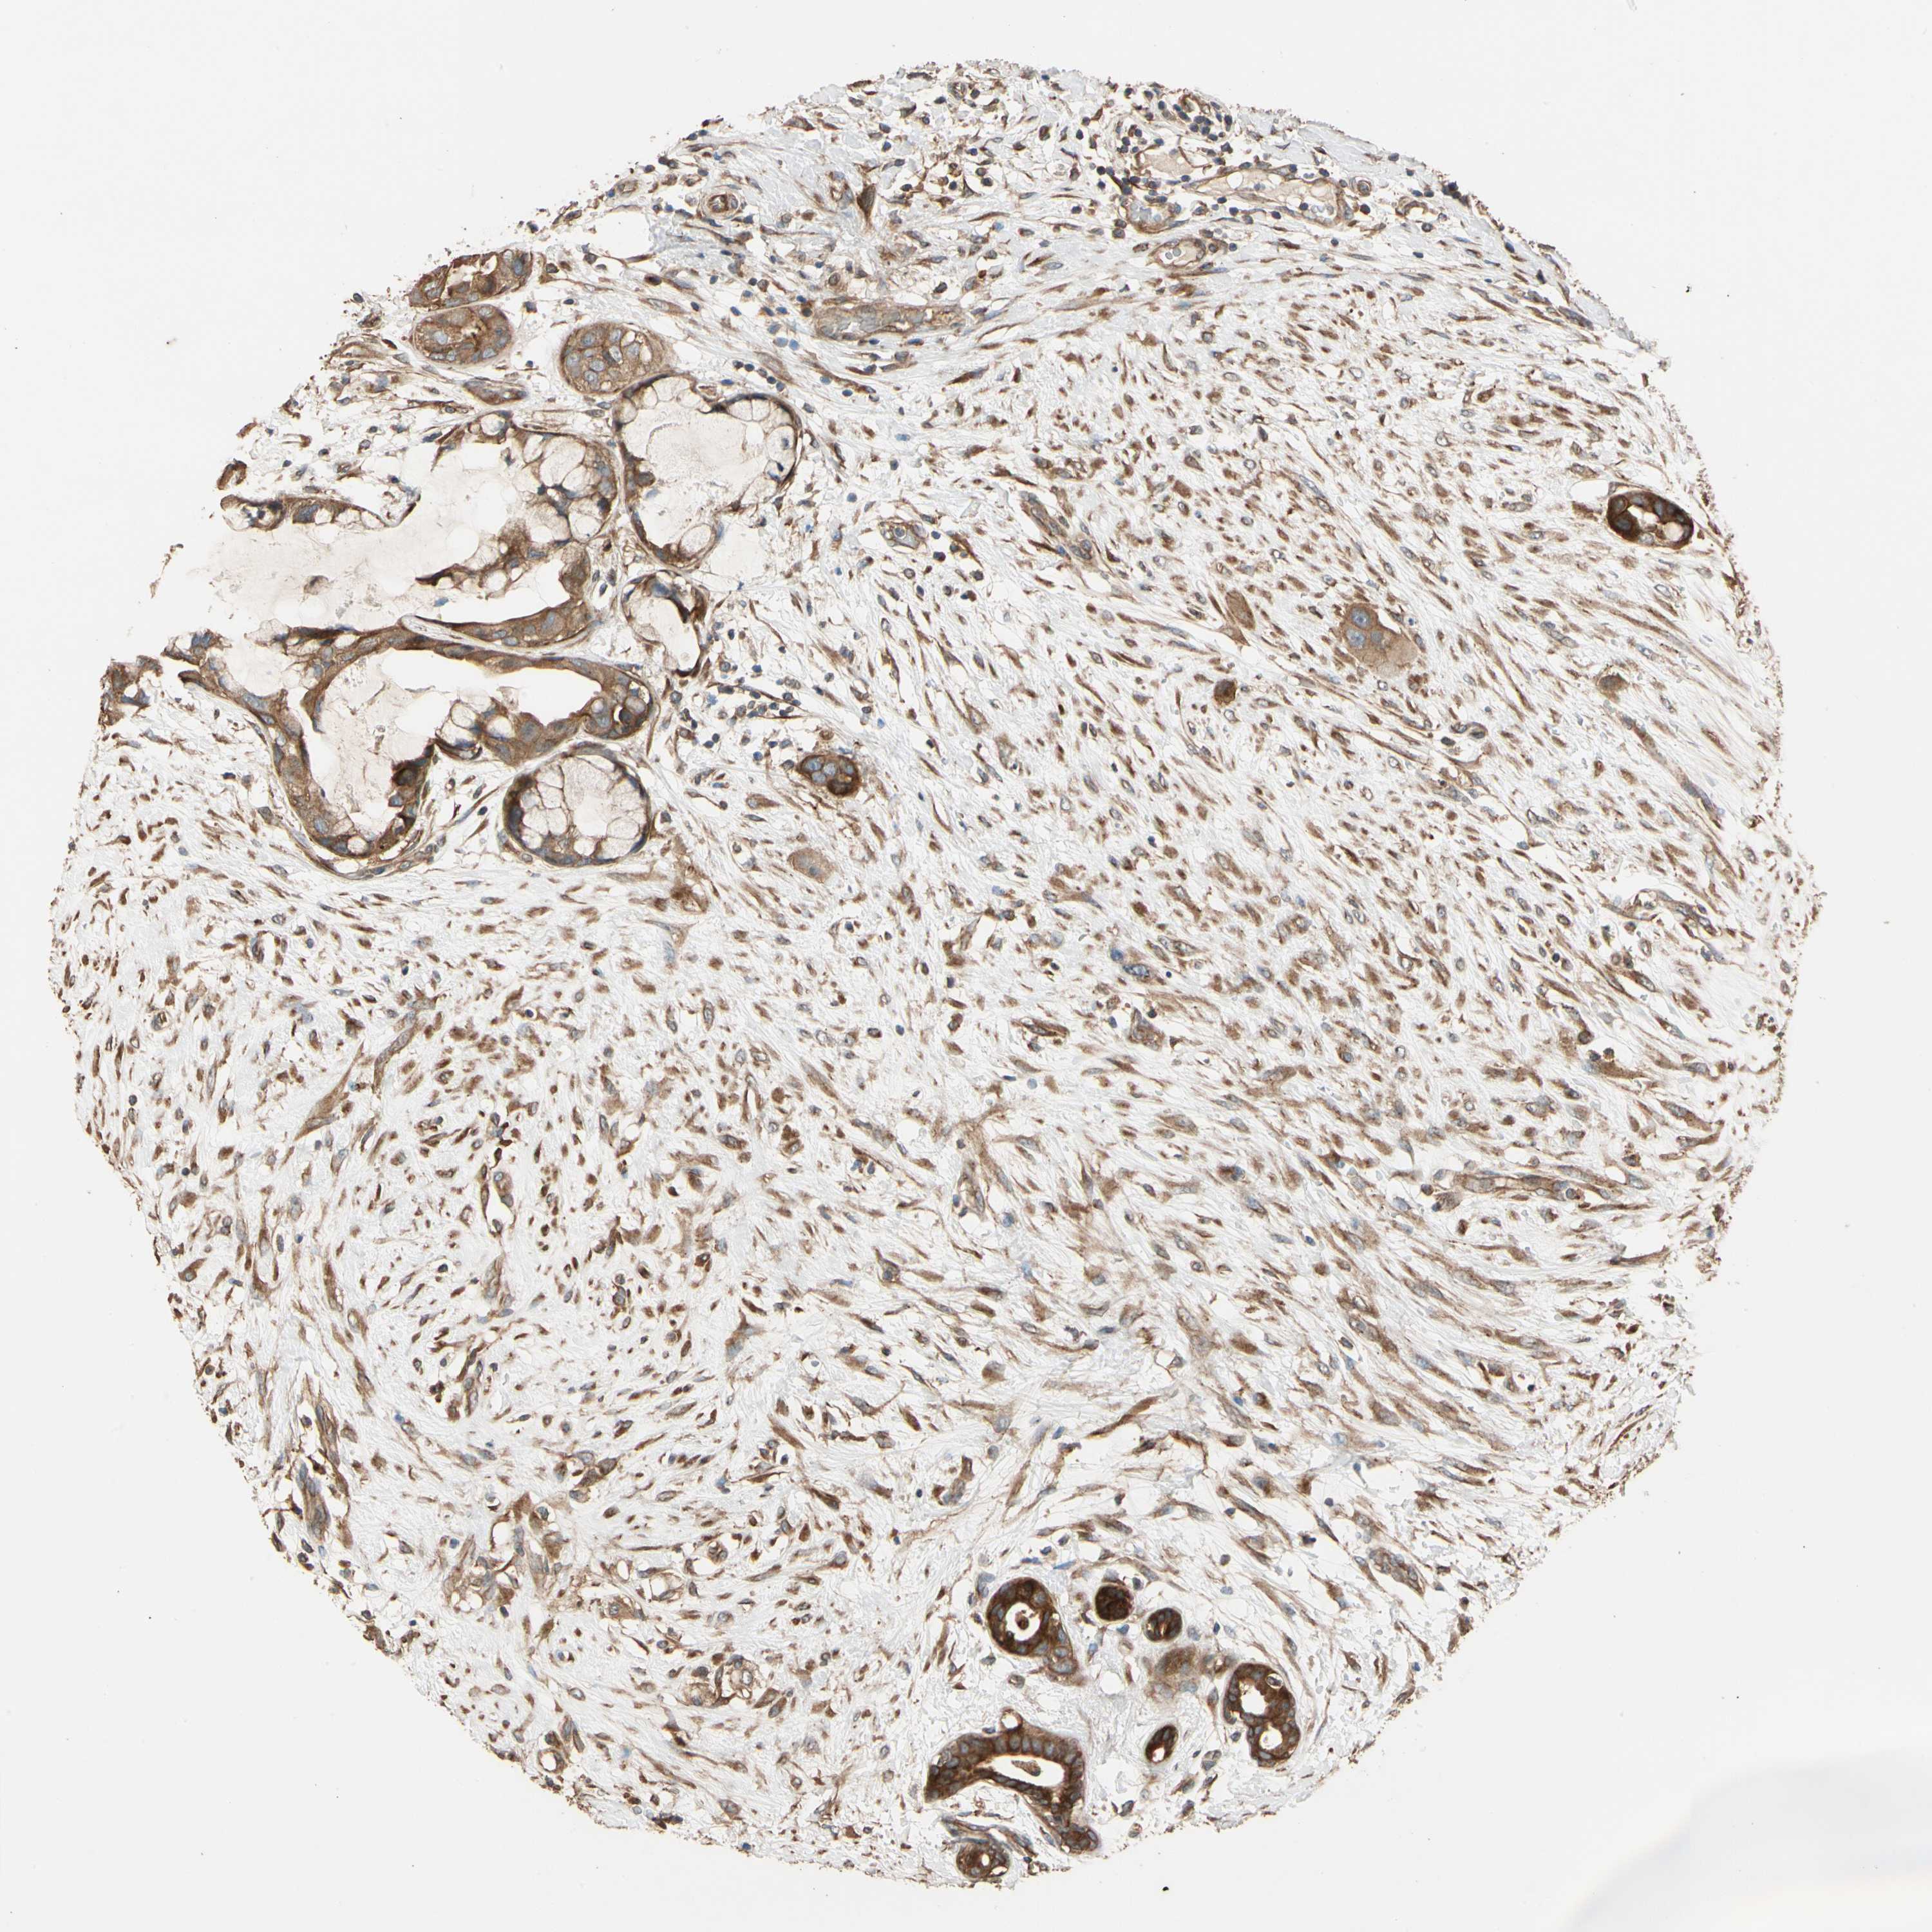

CANCER BREAST CANCER Show tissue menu

BRCA TCGA BRCA VALIDATION PROTEIN EXPRESSION